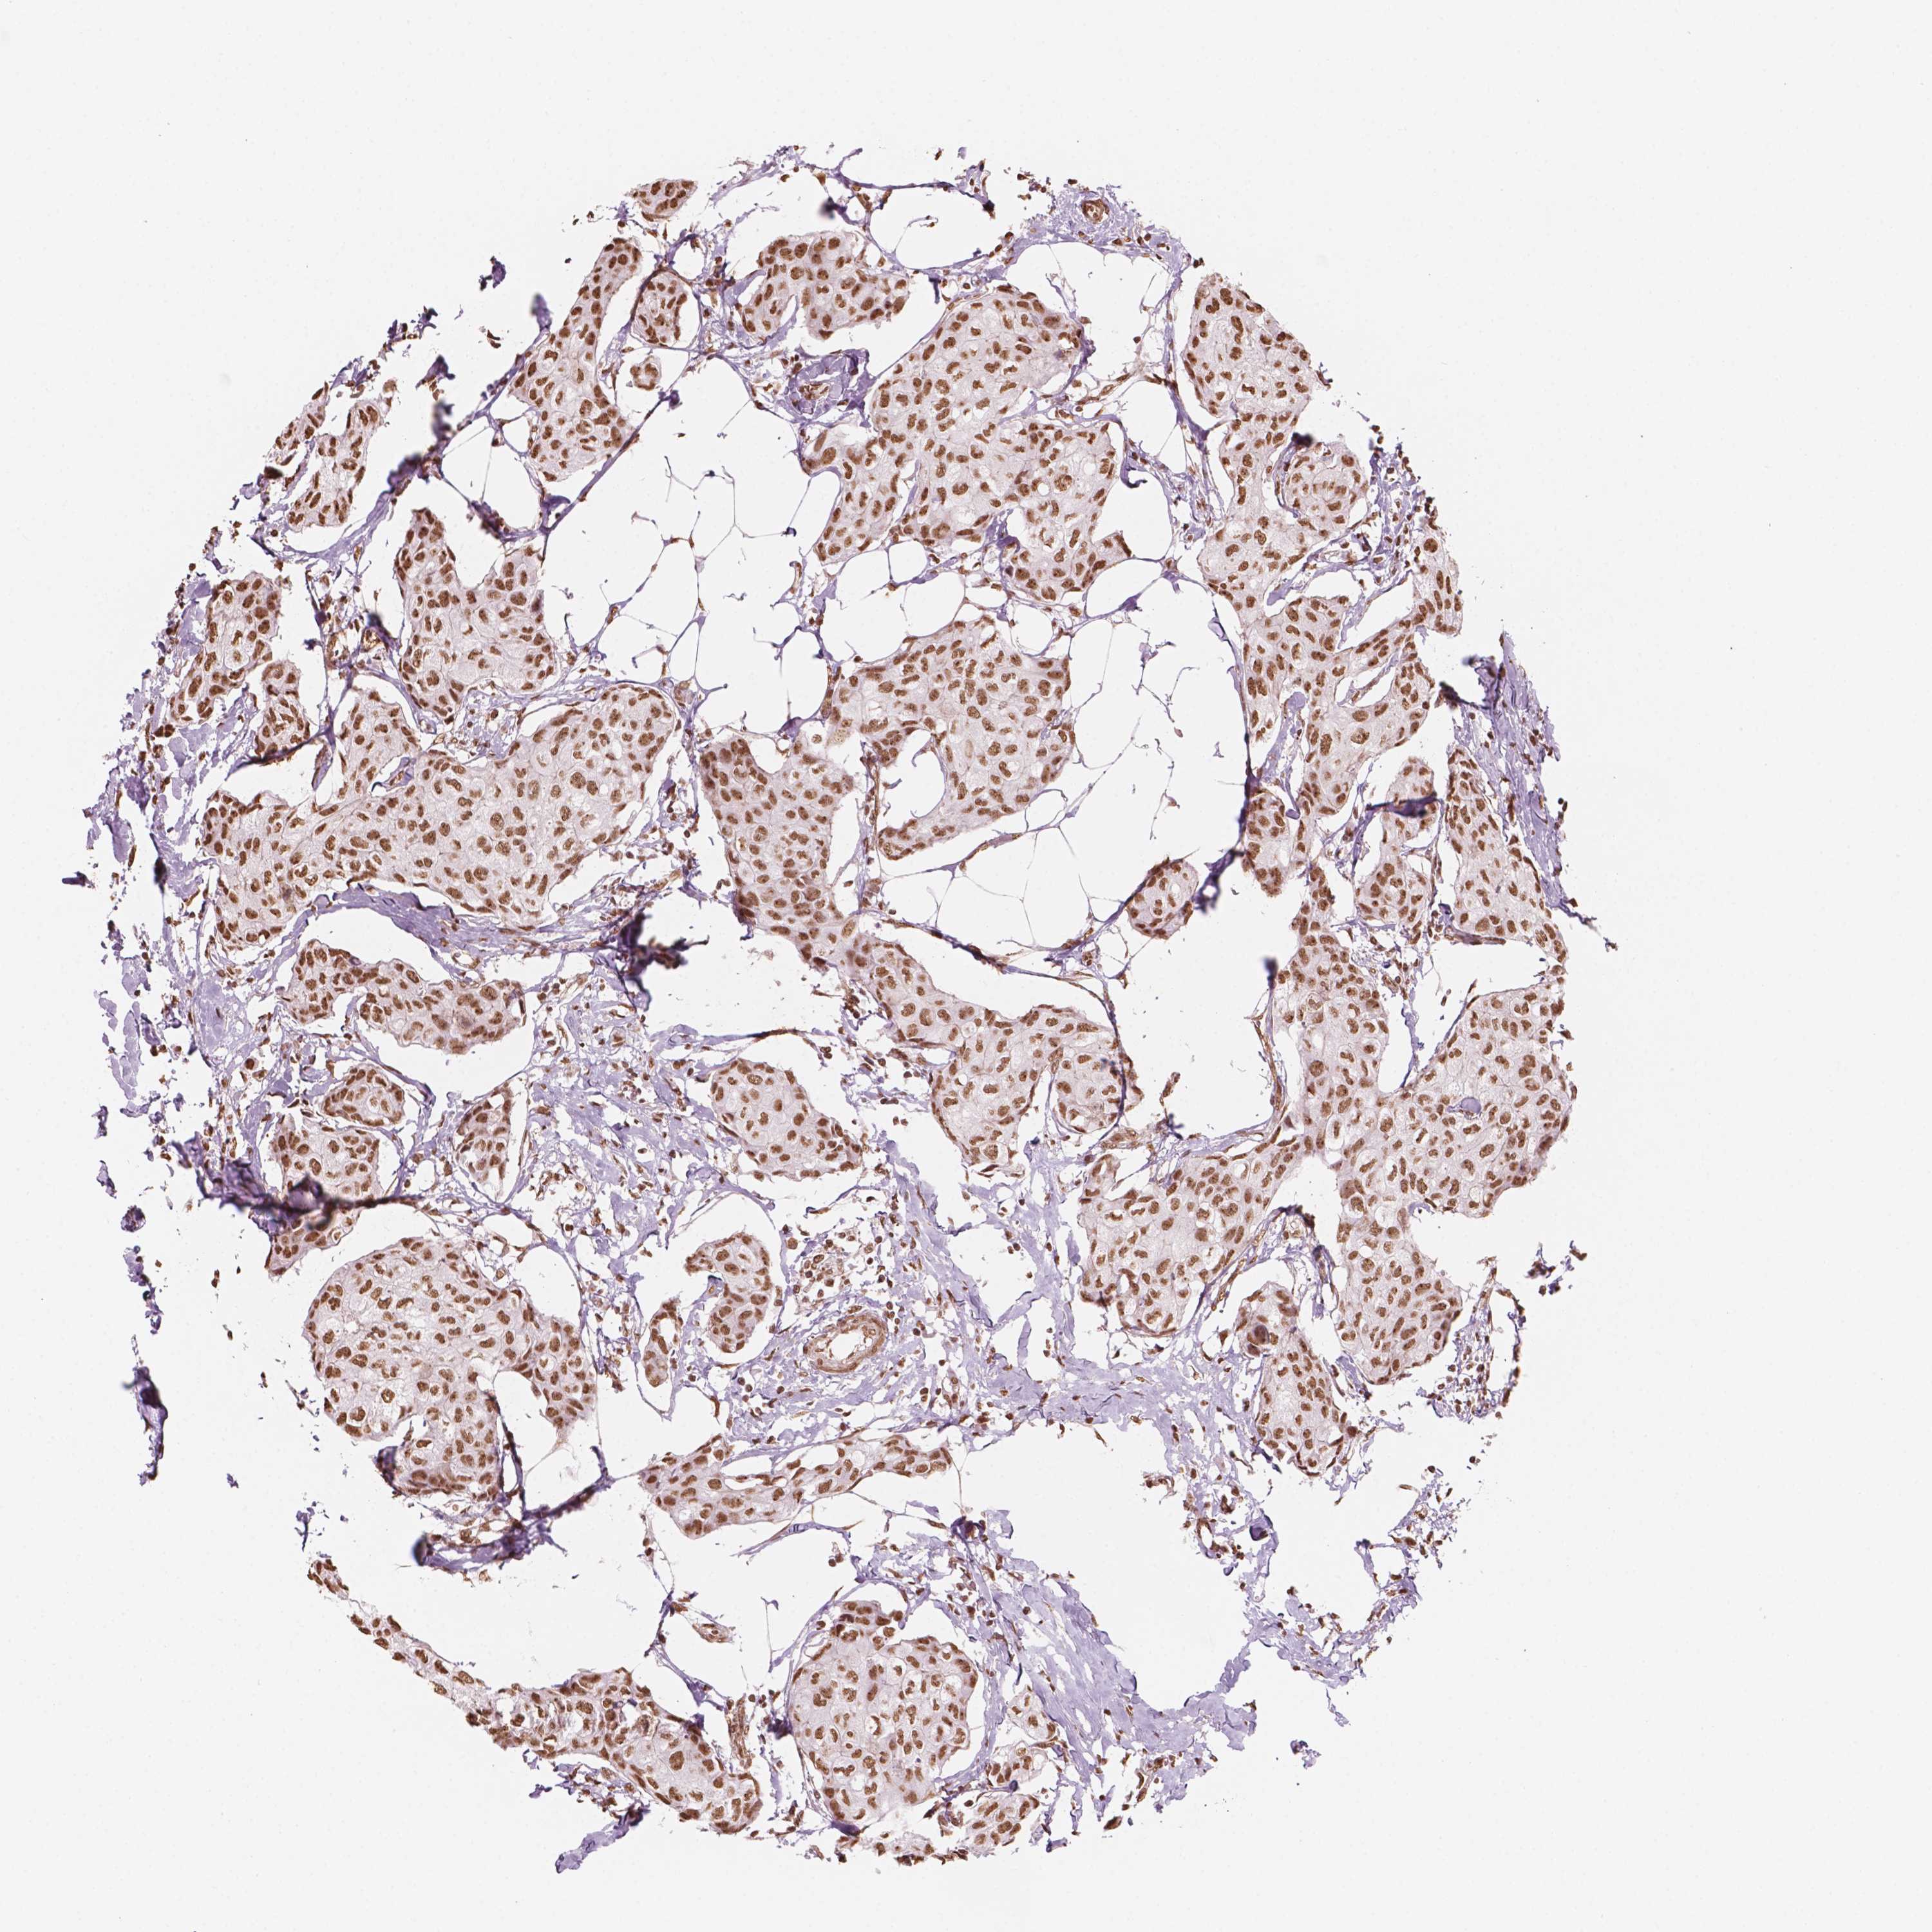

CANCER BREAST CANCER Show tissue menu

BRCA TCGA BRCA VALIDATION PROTEIN EXPRESSION